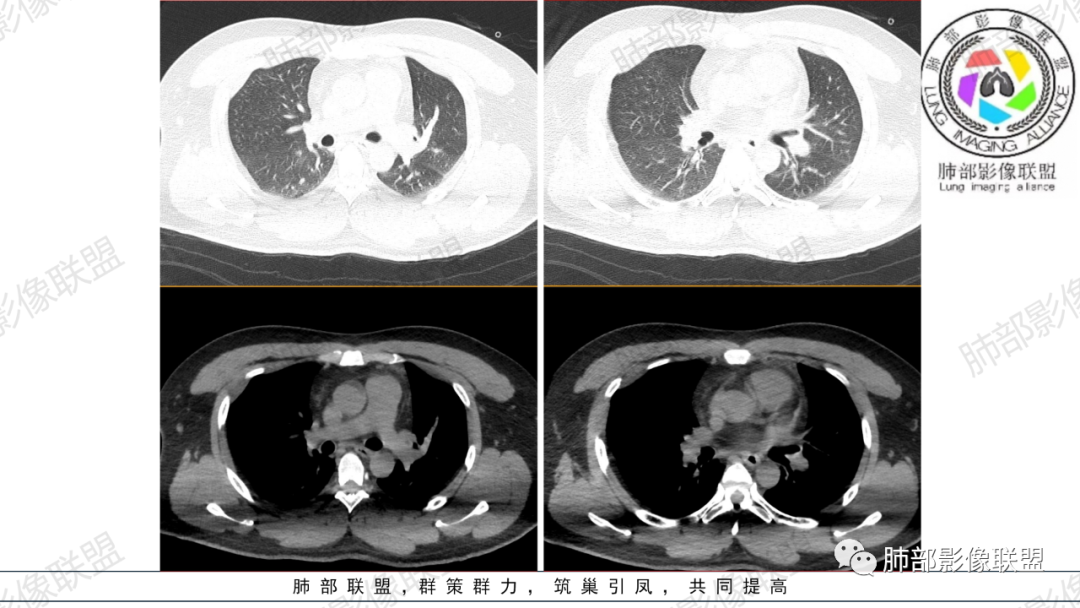

支气管痰栓或粘液阻塞,临床上并不少见,本例患者有腹部手术或胸部外伤肋骨骨折病史,其原因多是长时间采取一种被动体位,因怕疼痛而不敢咳嗽导致痰液引流不畅,自主排痰有一定的困难,导致痰液形成后不能及时排除。滞留痰液集聚形成痰块,混合坏死组织,部分形成痰栓。痰栓附着在气道壁上,局部气道变窄,如果不及时通畅气道,导致原来肺部、胸腔病变加重或出现新的病变,严重者可致局部气道闭塞,相应的肺叶出现肺不张CT上支气管粘液栓形态多样,可呈圆形,类圆形,条状、指套状、葡萄串状等。